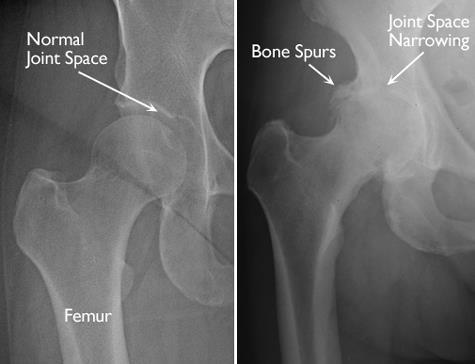

Describe three clinical features of osteoarthritis of the hip